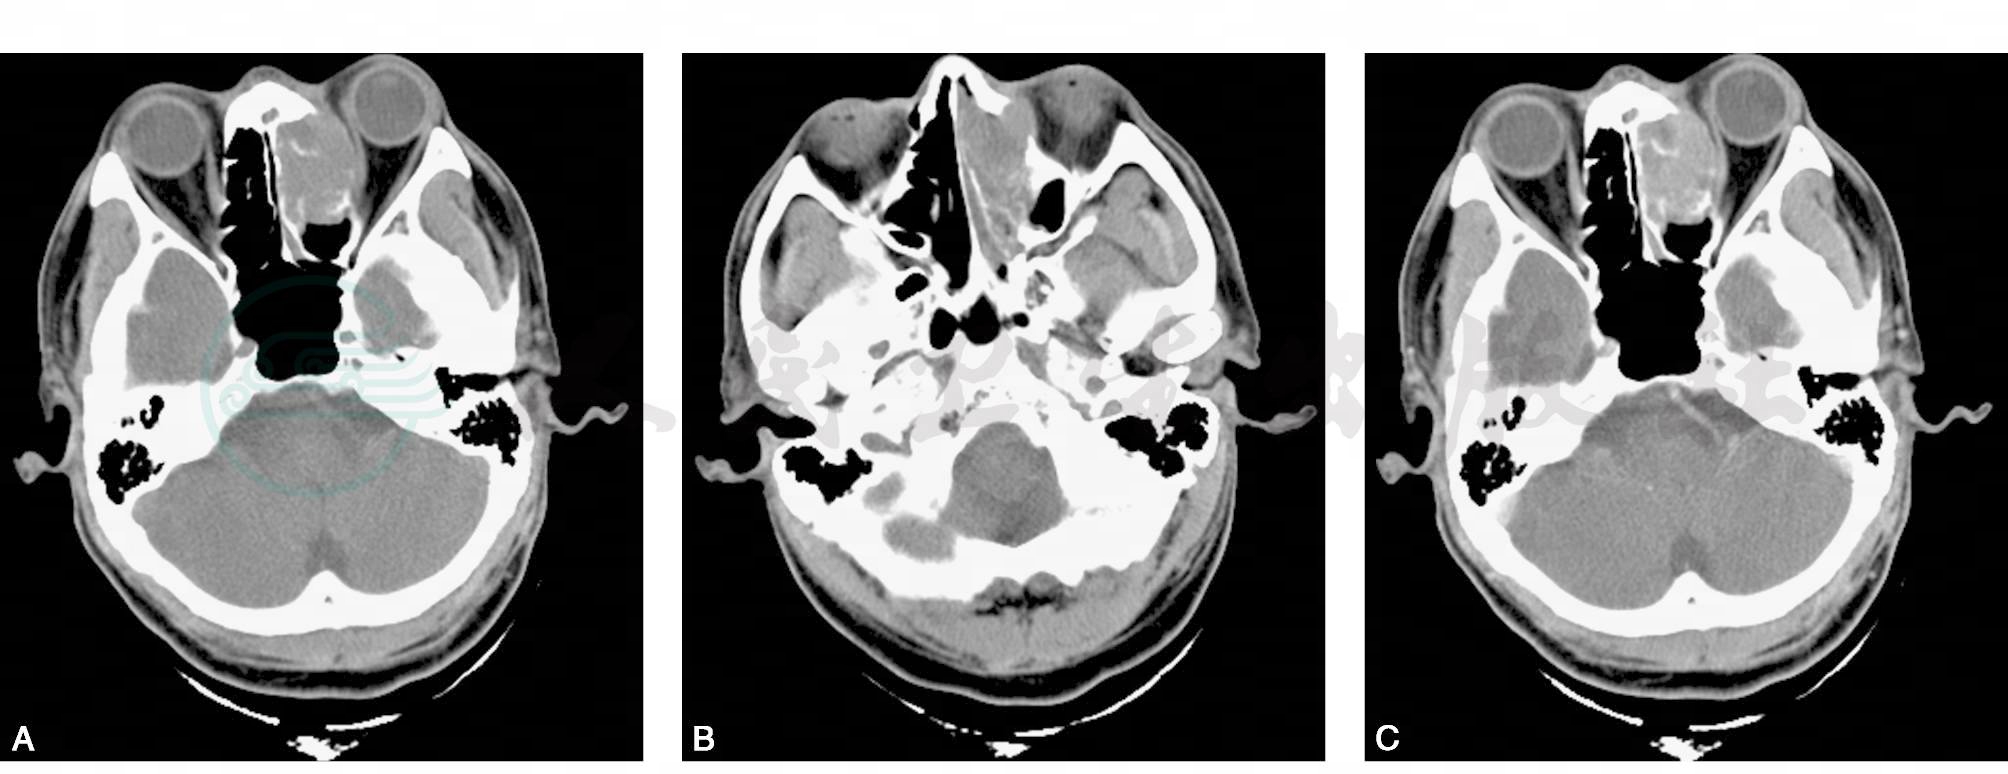

平扫横断面(图1A、B)示左侧筛窦内可见不规则软组织肿物,密度不均匀,左侧筛窦蜂房可见骨质破坏,肿物内可见条状残留骨质,肿物向左突入眼眶,左眼内直肌受压,向下侵犯左侧上颌窦。增强横断面(图1C、D)示肿物可见明显强化。骨窗横断面(图1E、F)示筛窦、眼眶内侧壁及上颌窦内侧壁可见骨质破坏。

图1 筛窦恶性黑色素瘤

A~B.平扫横断面;C~D.增强横断面;E~F.骨窗横断面;G.HE×200